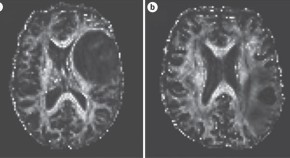

Conventional structural imaging provides limited information on tumor characterization and prognosis. Advances in neurosurgical techniques, radiotherapy planning and novel drug treatments for brain tumors have generated increasing need for reproducible, non-invasive, quantitative, imaging biomarkers. This Review discusses the role of physiological MRI and PET molecular imaging in understanding metabolic processes associated with tumor growth, blood flow and ultrastructure.